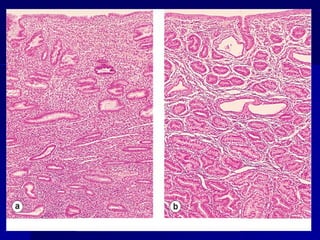

Atrofia glandular

prostática:

prostática: epitelio

epitelio

glandular prostático

aplanado, (H&E).

Proliferative endometrium

Atrophic endometrium